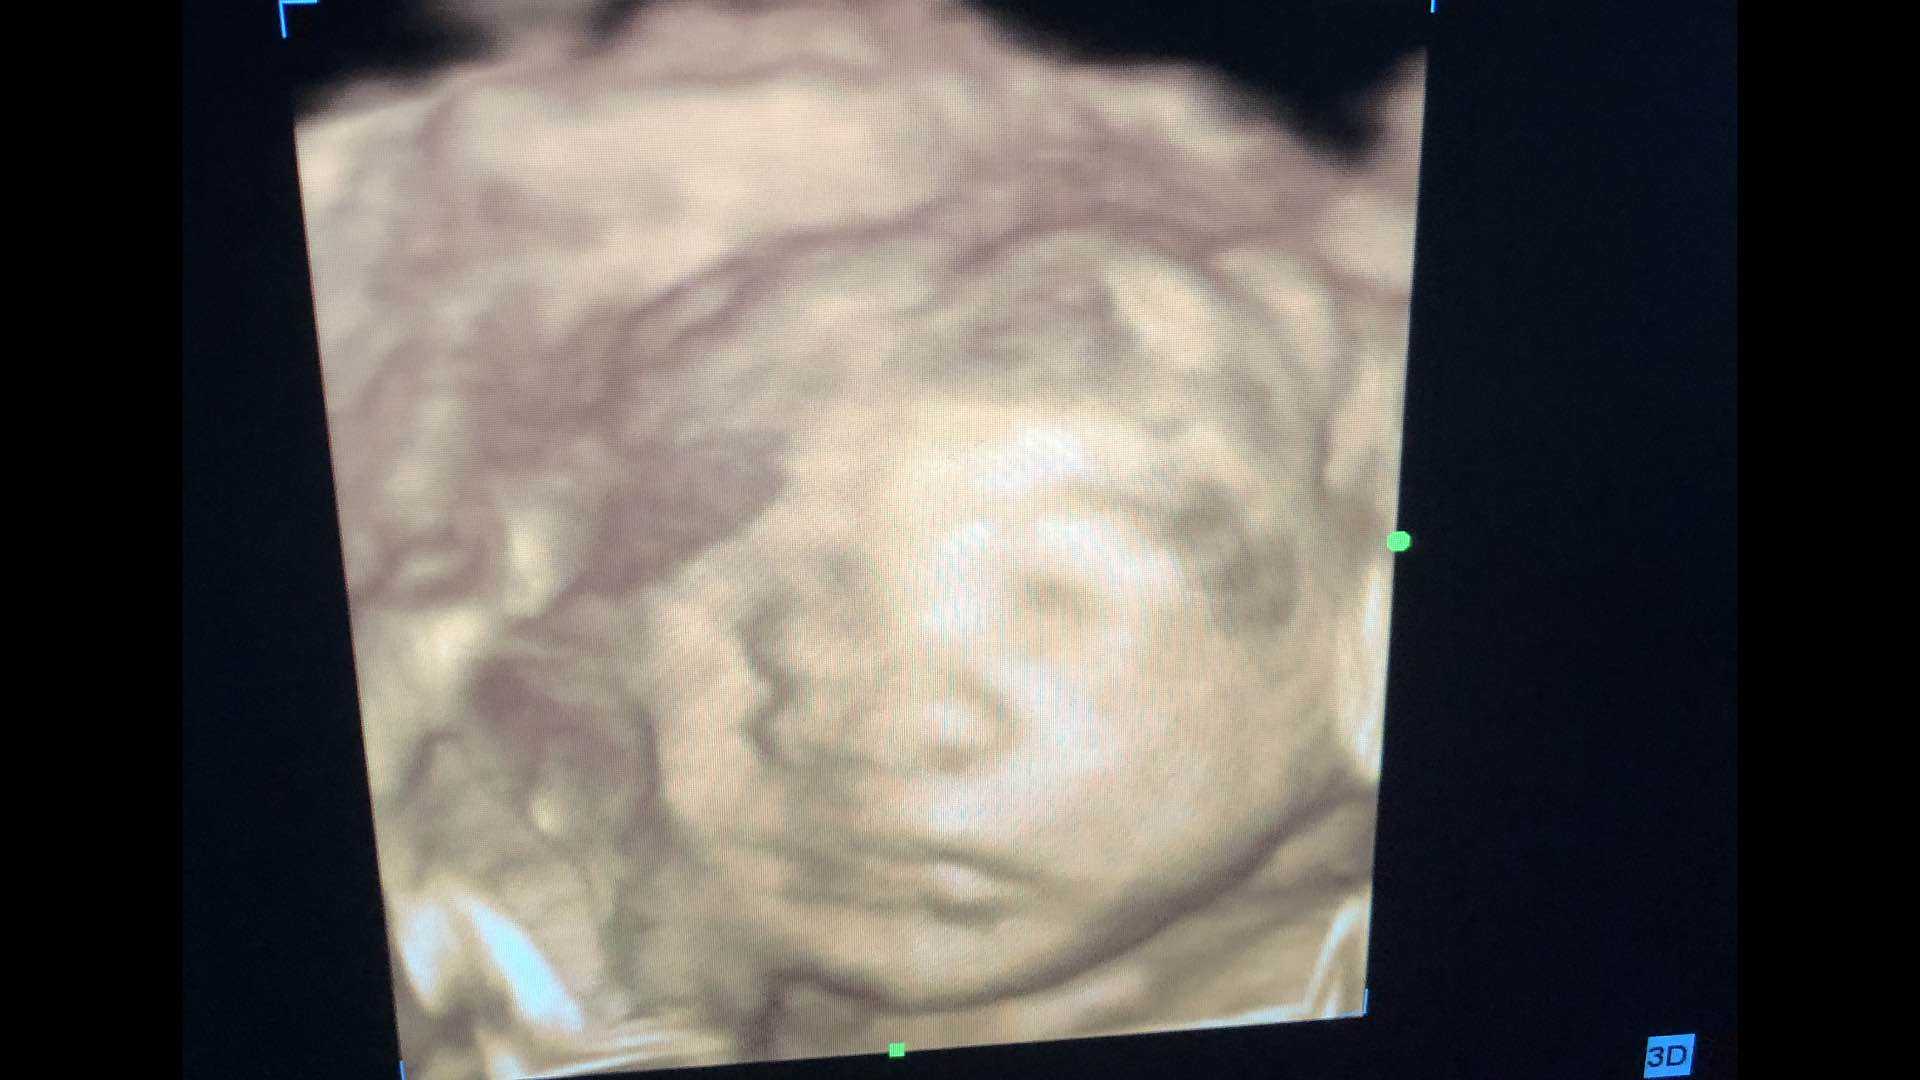

附宝宝四维照片嘴巴真的很像他老爹,大嘴巴,哈哈